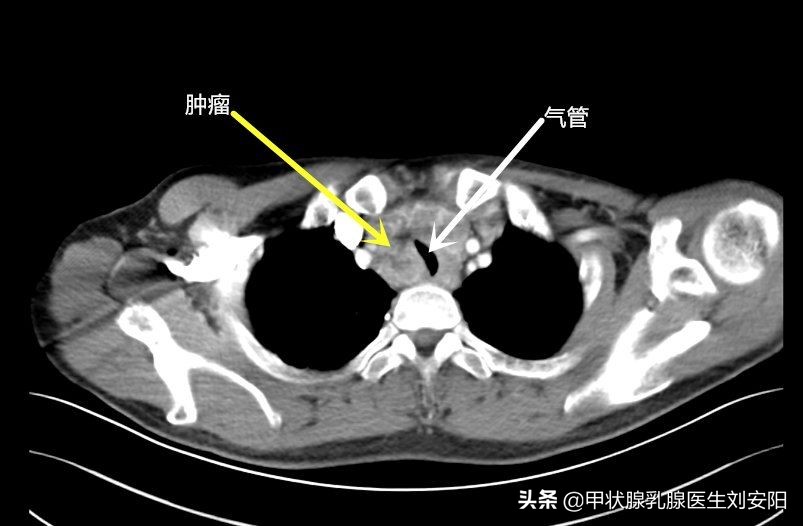

近日病房收治一名青年男性,确诊为甲状腺髓样癌,诊断时肿瘤已经侵犯气管,造成气管受压(CT见下图),憋气,此时手术比较困难。为什么没有早点发现呢?在询问病史的过程中,病人主诉反复腹泻已有一年余,当地医院做了大量关于消化道的检查,没有发现任何问题,等出现了呼吸困难时才开始关注胸部及甲状腺,行颈胸部CT发现肿物并诊断为甲状腺髓样癌,若在一年前发现,治疗会相对容易一些,治疗效果也会好。那么究竟什么是甲状腺髓样癌,为什么会导致腹泻,如何早期发现、早期治疗呢?